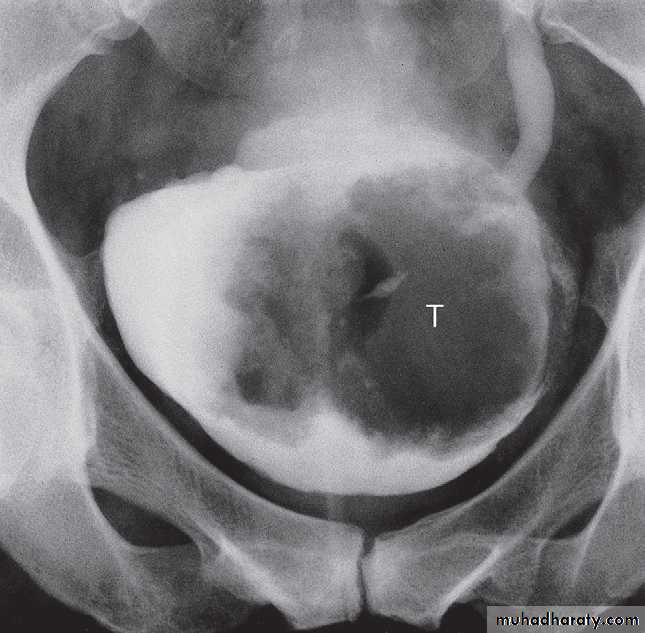

On CT and MRI, a bladder tumour is seen as a soft tissue mass projecting from the wall or a focal thickening of the bladder wall . As the diagnosis is best established by cystoscopy and biopsy, the roles of CT and MRI are to stage the tumour. CT and MRI can determine the spread of tumour beyond the bladder wall and assess lymph node involvement .

Prostate and urethra disorders (Prostatic enlargement)

Prostatic enlargement is very common in elderly men. It is usually due to benign hypertrophy but may be due to carcinoma.Prostatic ultrasound uses a

Computed tomography does not demonstrate the internal structure of the prostate , so of little value in evaluation prostatic lesion .

Magnetic resonance imaging is best imaging modality for staging , used to assess early stage prostate cancer in patients being considered for radical surgery or radiotherapy. Tumour in the peripheral zone is seen as a relatively low signal mass within the normal high signal of the peripheral zone on T2-weighted images.

MRI is used to demonstrate extracapsular tumour spread, to show invasion of the seminal vesicles, and to demonstrate possible lymph

node metastases .